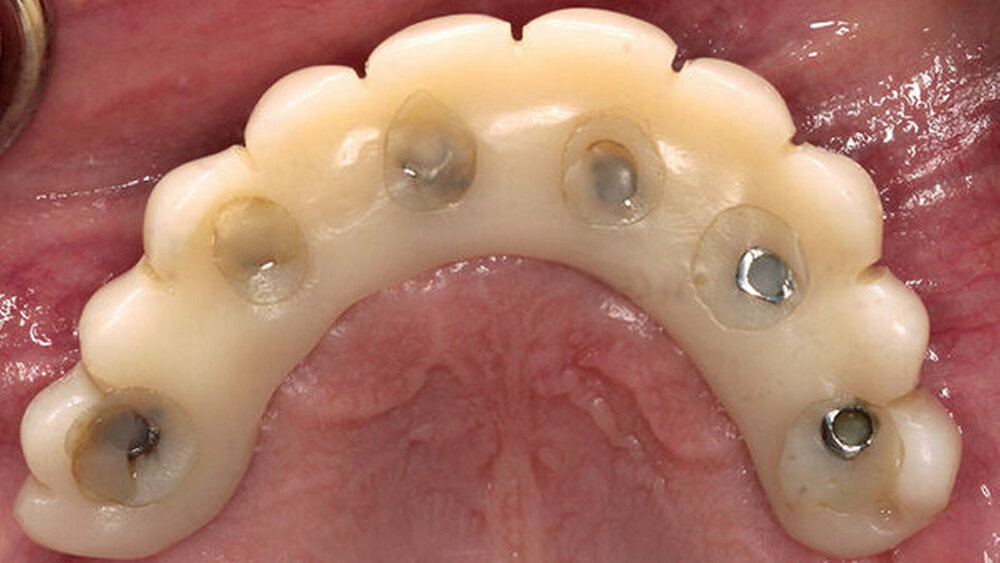

Buhtz: Korrekt, die Voraussetzung ist lediglich die Generierung von DICOM- und STL-Daten, die im Computer exakt übereinandergelegt werden können. Dann erfolgen die Behandlungsplanung wie gewohnt mit ICX-Magellan und die provisorische ‧Versorgung mit dem präfabizierten, chairside hergestellten verklebten PMMA-Provisorium (ICX-‧Smile‧bridge). Seit eineinhalb Jahren arbeiten wir zudem mit dem medentis Fräszentrum Denta5 zusammen.

Buhtz: Wir schicken die Scan-Daten, ein Wax-up und ggf. das Modell mit den Laborimplantaten an das medentis-Fräszentrum und erhalten zwei Tage später die verschraubte Unterkonstruktion. Denta 5 gibt es bereits seit einigen Jahren. Doch erst seit wir einen eigenen Modellscanner haben, stellen wir verschraubte Brücken auf diese Weise her. Jetzt habe ich eine Zahntechnikerin, die damit gut klarkommt. Full-arch-Versorgungen sind bei uns allerdings nicht das Tagesgeschäft, wir machen das vielleicht zehn- bis zwanzigmal pro Jahr. Unsere Patientenklientel ist in der Regel nicht zahnlos.